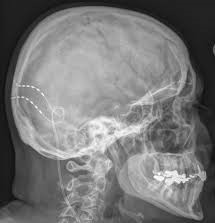

Η περιφερική νευροδιέγερση αφορά σε εμφύτευση υποδόριων ηλεκτροδίων στην περιοχή κατανομής των ινιακών νεύρων. Η τεχνική αποτελεί μια  πολύ αποτελεσματική μέδοδο αντιμετώπισης ανθεκτικών μορφών της πάθησης που δεν ανταποκρίνονται σε άλλες λιγότερο παρεμβατικές θεραπείες.